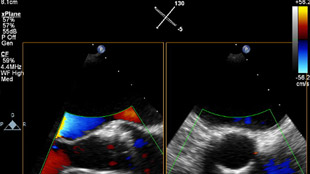

Uw patiënt is gediagnosticeerd met symptomatische aortastenose. Ze is 85 jaar, heeft diabetes en een hoge bloeddruk. U weet dat ze een verhoogd risico loopt en niet in aanmerking komt voor hartchirurgie, maar misschien wel voor transkatheter aortaklepvervanging (TAVR). Vandaag de dag bieden innovatieve beeldvormingsoplossingen en percutane instrumenten hoop voor sommige patiënten die tot nu toe geen andere opties hadden .